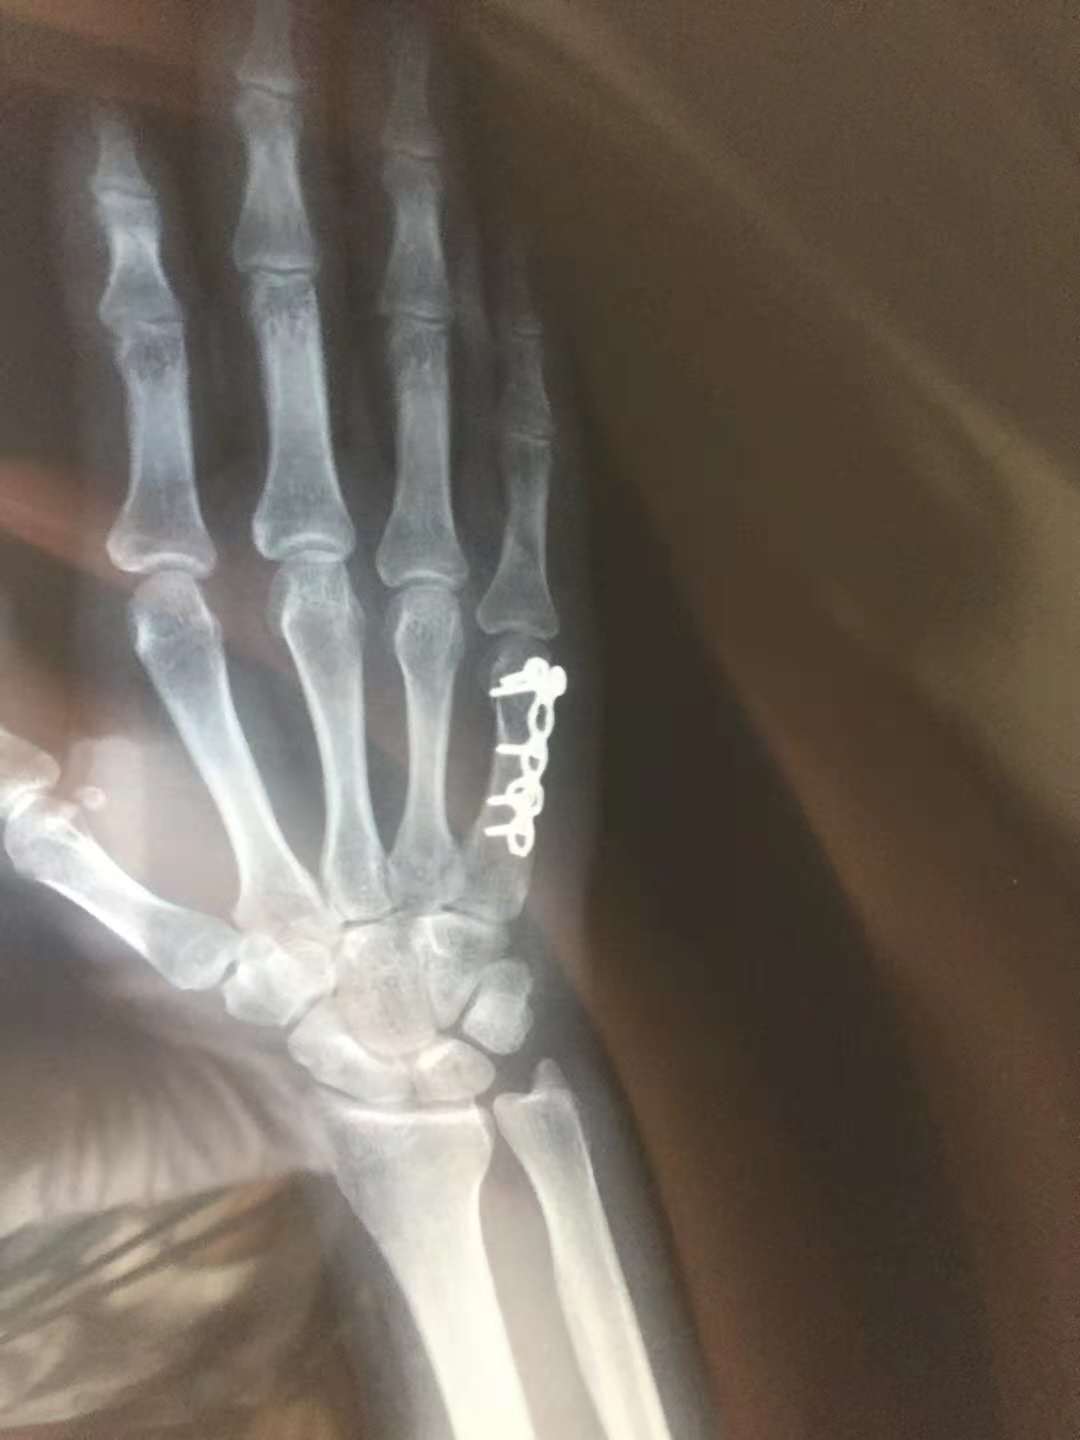

3.切开复位钢板固定

对于难复性,或者复位后维持不住的患者,或者粉碎较重,对手指活动要求较高的职业。